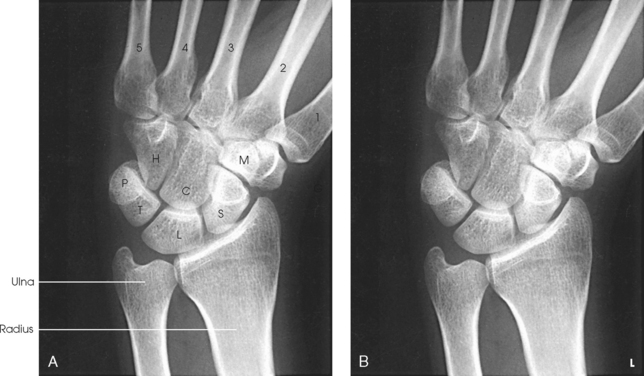

The wrist has eight carpal bones, which are fitted closely together and arranged in two horizontal rows (see Fig. 4-1). The carpals are classified as short bones and are composed largely of cancellous tissue with an outer layer of compact bony tissue. These bones, with one exception, have two or three names; this atlas uses the preferred terms (see box). The proximal row of carpals, which is nearest the forearm, contains the scaphoid, lunate, triquetrum, and pisiform. The distal row includes the trapezium, trapezoid, capitate, and hamate.

Each carpal contains identifying characteristics. Beginning at the proximal row of carpals on the lateral side, the scaphoid, the largest bone in the proximal carpal row, has a tubercle on the anterior and lateral aspect for muscle attachment and is palpable near the base of the thumb. The lunate articulates with the radius proximally and is easy to recognize because of its crescent shape. The triquetrum is roughly pyramidal and articulates anteriorly with the hamate. The pisiform is a pea-shaped bone situated anterior to the triquetrum and is easily palpated.

Beginning at the distal row of carpals on the lateral side, the trapezium has a tubercle and groove on the anterior surface. The tubercles of the trapezium and scaphoid constitute the lateral margin of the carpal groove. The trapezoid has a smaller surface anteriorly than posteriorly. The capitate articulates with the base of the third metacarpal and is the largest and most centrally located carpal. The wedge-shaped hamate exhibits the prominent hook of hamate, which is located on the anterior surface. The hamate and the pisiform form the medial margin of the carpal groove.

The carpals articulate with each other, the metacarpals, and the radius of the forearm. In the carpometacarpal (CMC) articulations, the first metacarpal and trapezium form a synovial saddle joint, which permits the thumb to oppose the fingers (touch the fingertips). The articulations between the second, third, fourth, and fifth metacarpals and the trapezoid, capitate, and hamate form synovial gliding joints. The intercarpal articulations are also synovial gliding joints. The articulations between the lunate and scaphoid form a gliding joint. The radiocarpal articulation is a synovial ellipsoidal type. This joint is formed by the articulation of the scaphoid, lunate, and triquetrum, with the radius and the articular disk just distal to the ulna (Fig. 4-9, C).